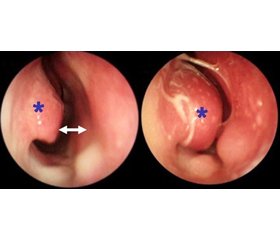

Меньшая выраженность проявлений КАР по сравнению с САР связана с меньшей концентрацией антигенов (АГ). Нередко единственной жалобой является заложенность носа. Из-за этого страдает носоглотка, сон, появляются храп, отит, носовые кровотечения у детей. У пациентов постоянно заложен нос, даже в период ремиссии. Выделения из носа — преимущественно слизистые. Типичными являются утренние приступы. У больных может наблюдаться дисфункция евстахиевой трубы, тимпанит.

Наблюдается выраженная эозинофилия секрета. Соотношение уровней эозинофилов и нейтрофилов — важный показатель роли инфекции. В назальном секрете в значительном количестве обнаруживаются тучные клетки, базофилы, часто повышен уровень иммуноглобулинов классов IgA, IgG, IgE. На рентгенограмме может проявляться затемнение лобных и решетчатых пазух носа. У 20–40 % больных выявляются синуситы [4, 5].